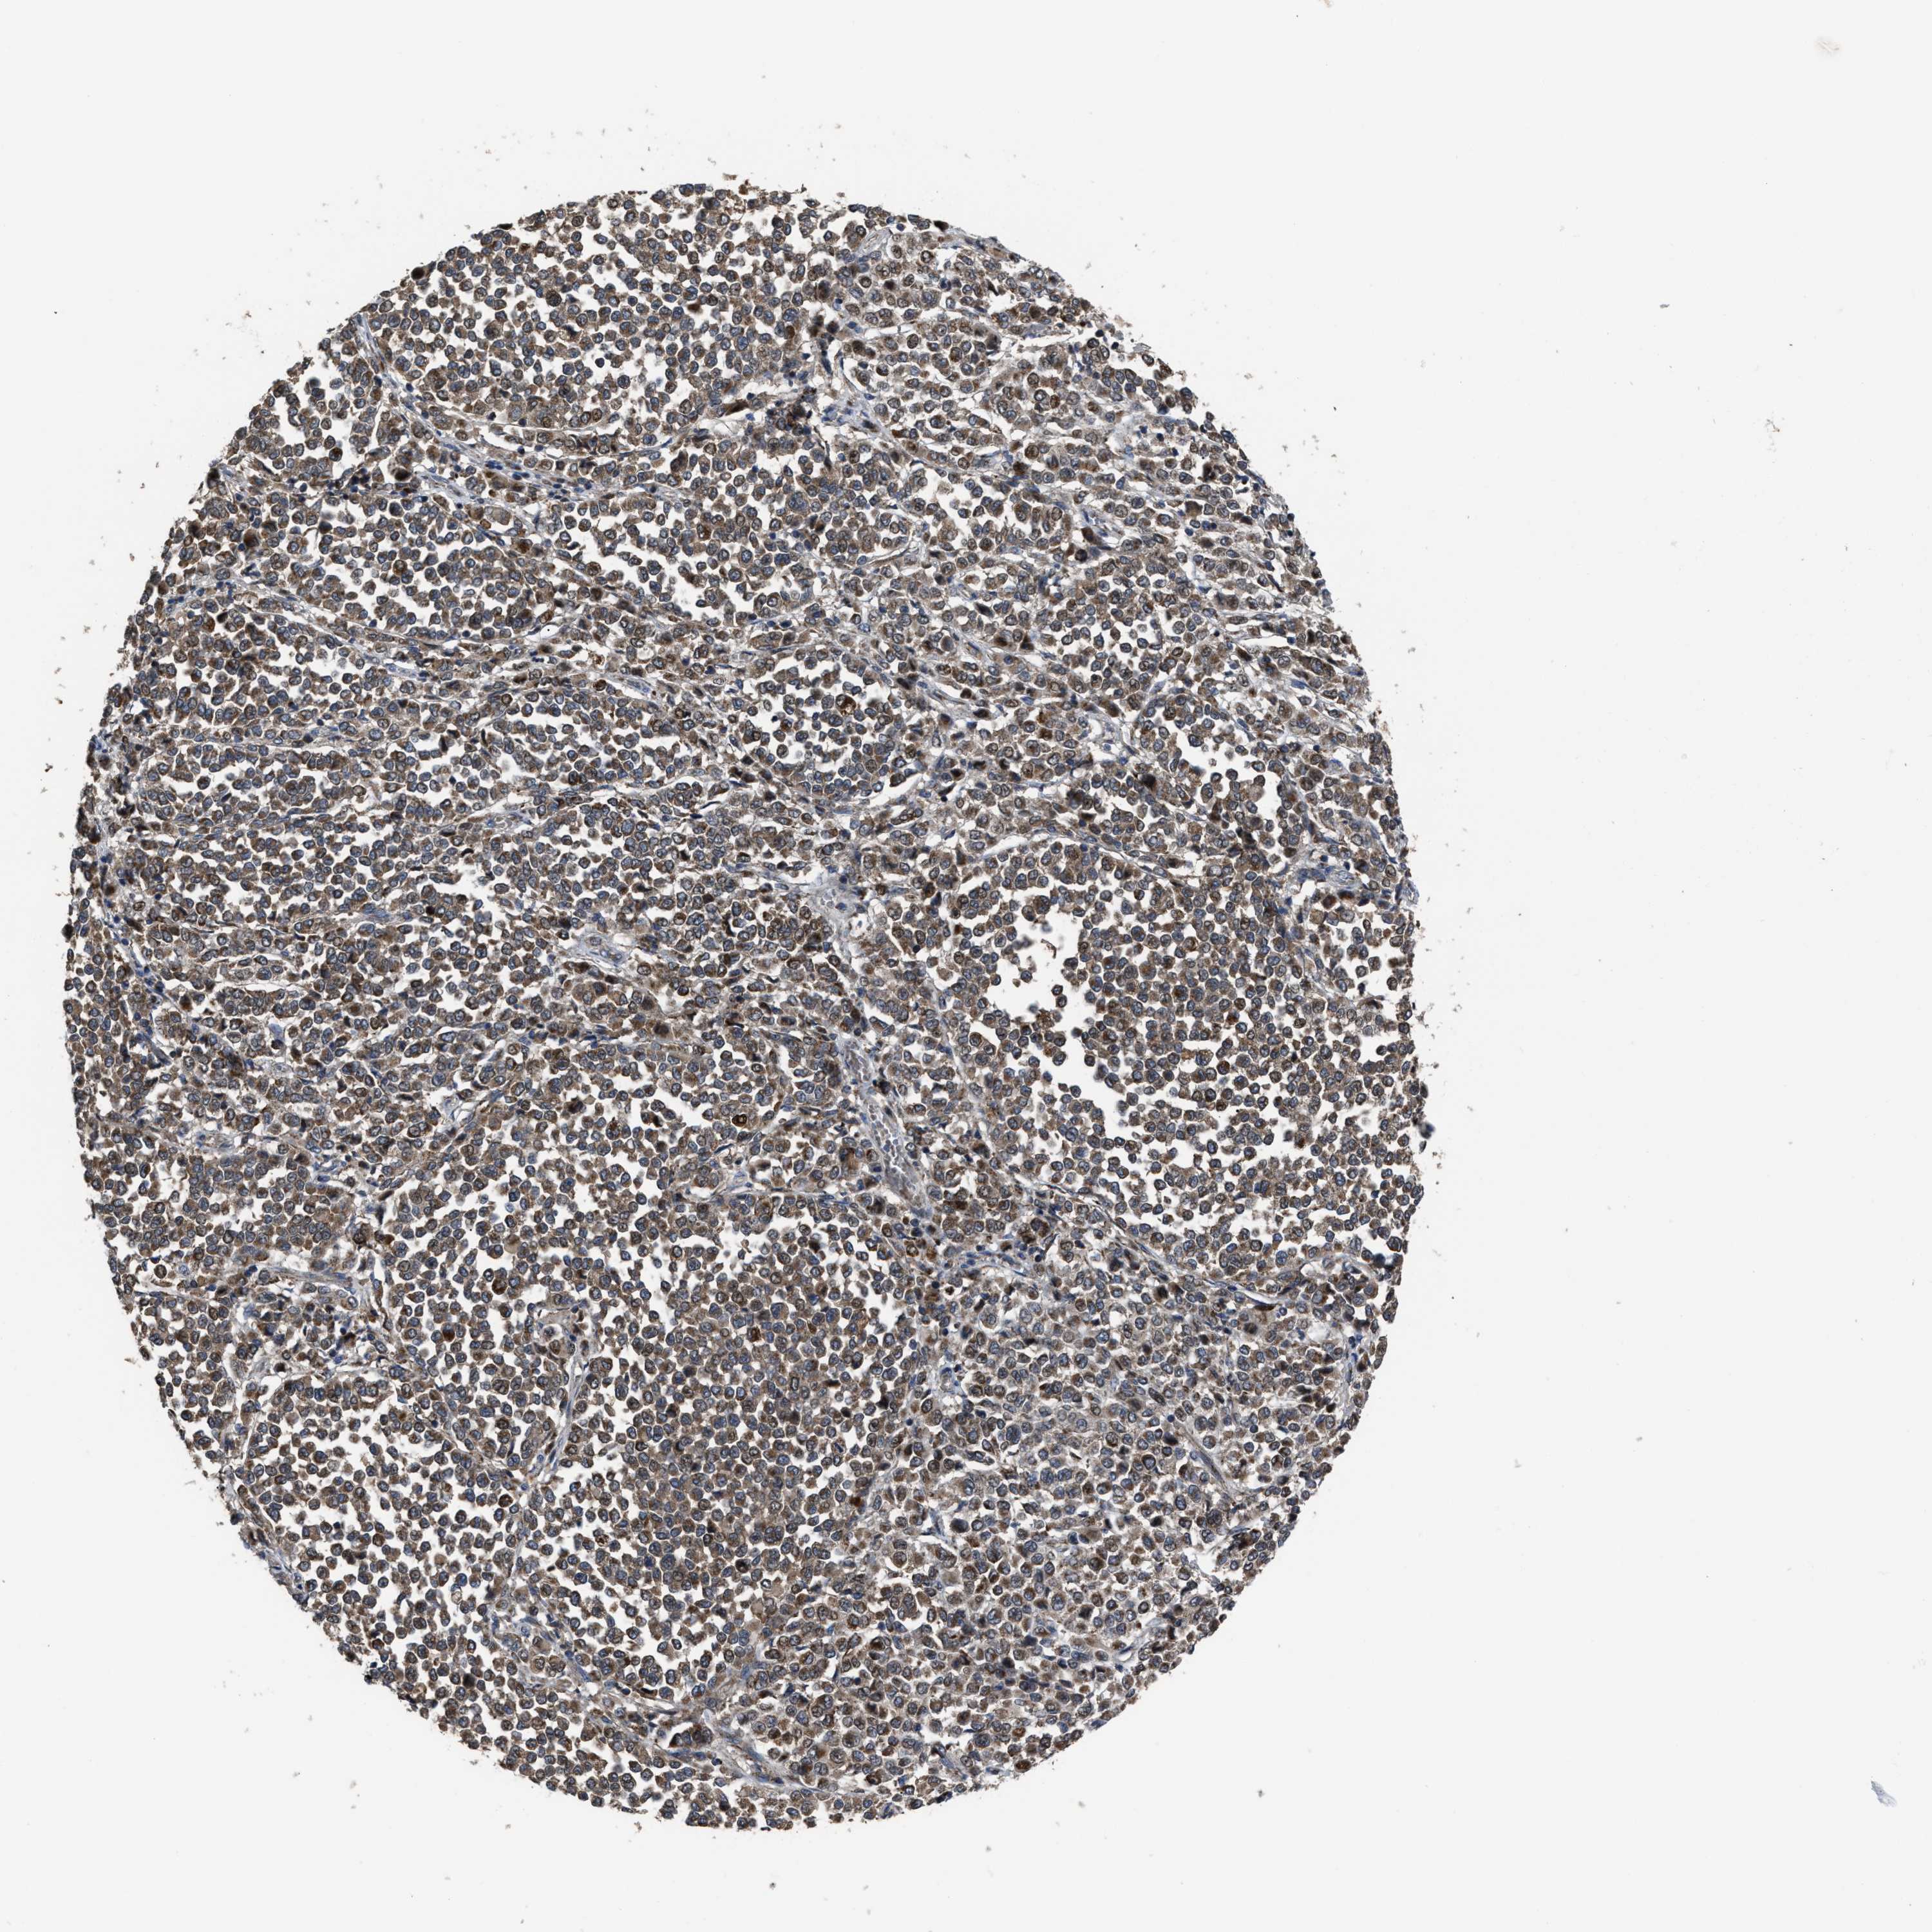

MELANOMA - Protein expressioni

A mouse-over function shows sample information and annotation data. Click on an image to view it in a full screen mode. Samples can be filtered based on level of antibody staining by selecting one or several of the following categories: high, medium, low and not detected. The assay and annotation is described here.

Note that samples used for immunohistochemistry by the Human Protein Atlas do not correspond to samples in the TCGA dataset.

Antibody stainingi

Antibody staining in the annotated cell types in the current human tissue is reported as not detected, low, medium, or high, based on conventional immunohistochemistry profiling in selected tissues. This score is based on the combination of the staining intensity and fraction of stained cells.

Each image is clickable and will lead to virtual microscopy that enables deeper exploration of all samples and also displays staining intensity scores, fraction scores and subcellular localization as well as patient and tissue information for each sample.

Antibody HPA016450

Antibody HPA021079

Staining

High

Medium

Low

Not detected

Intensity

Strong

Moderate

Weak

Negative

Quantity

>75%

75%-25%

<25%

None

Location

Nuclear

Cytoplasmic/membranous

Cytoplasmic/membranous,nuclear

Malignant melanoma, NOS

Malignant melanoma, Metastatic site